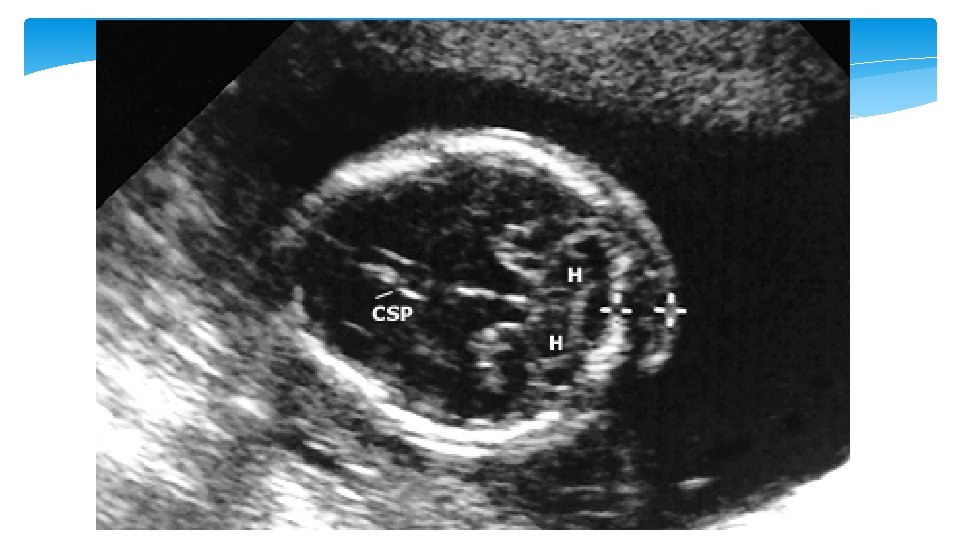

Mild ventriculomegaly Ventriculomegaly is a condition caused when there is dilated atrium beyond 10 mm. The mild ventriculomegaly (MVM), or what is called borderline ventriculomegaly, range between 10 – 12 mm and 10– 15 mm. It can be an isolated finding or be associated with an underlying cranial defect or anomaly such as agenesis of the corpus callosum

Ventriculomegaly Isolated ventriculomegaly is a risk factor for Down syndrome Mild ventriculomegaly is detected in 4 to 13 percent of fetuses with Down syndrome and 0. 1 to 0. 4 percent of euploid fetuses The risk of abnormal outcome, such as Down syndrome, increases with the degree of ventriculomegaly, progression of ventriculomegaly, and presence of other anomalies.

Soft marker Second trimester: echogenic bowel Second trimester: thickened nuchal fold Second trimester: mild ventriculomegaly Imaging criteria Aneuploidy association Management Fetal small bowel as echogenic as bone • LR 5. 5 to 6. 7 for Down syndrome • Associated with aneuploidy, intraamniotic bleeding, CF, CMV 1. Further counseling 2. Offer CMV, CF, and aneuploidy screening or diagnostic testing ≥ 6 mm from outer edge of the occipital bone to outer skin in the midline • LR 11 to 18. 6 with 40 to 50% sensitivity and >99% specificity for Down syndrome • Most powerful secondtrimester marker 1. Detailed anatomic survey 2. Further detailed genetic counseling and aneuploidy screening or diagnostic testing • Associated with aneuploidy • LR 25 for Down syndrome 1. Genetic counseling 2. Second-trimester detailed anatomic ultrasound evaluation 3. Consider diagnostic testing for aneuploidy and CMV 4. Repeat ultrasound in third trimester Lateral ventricular atrial measurement between 10 to 15 mm